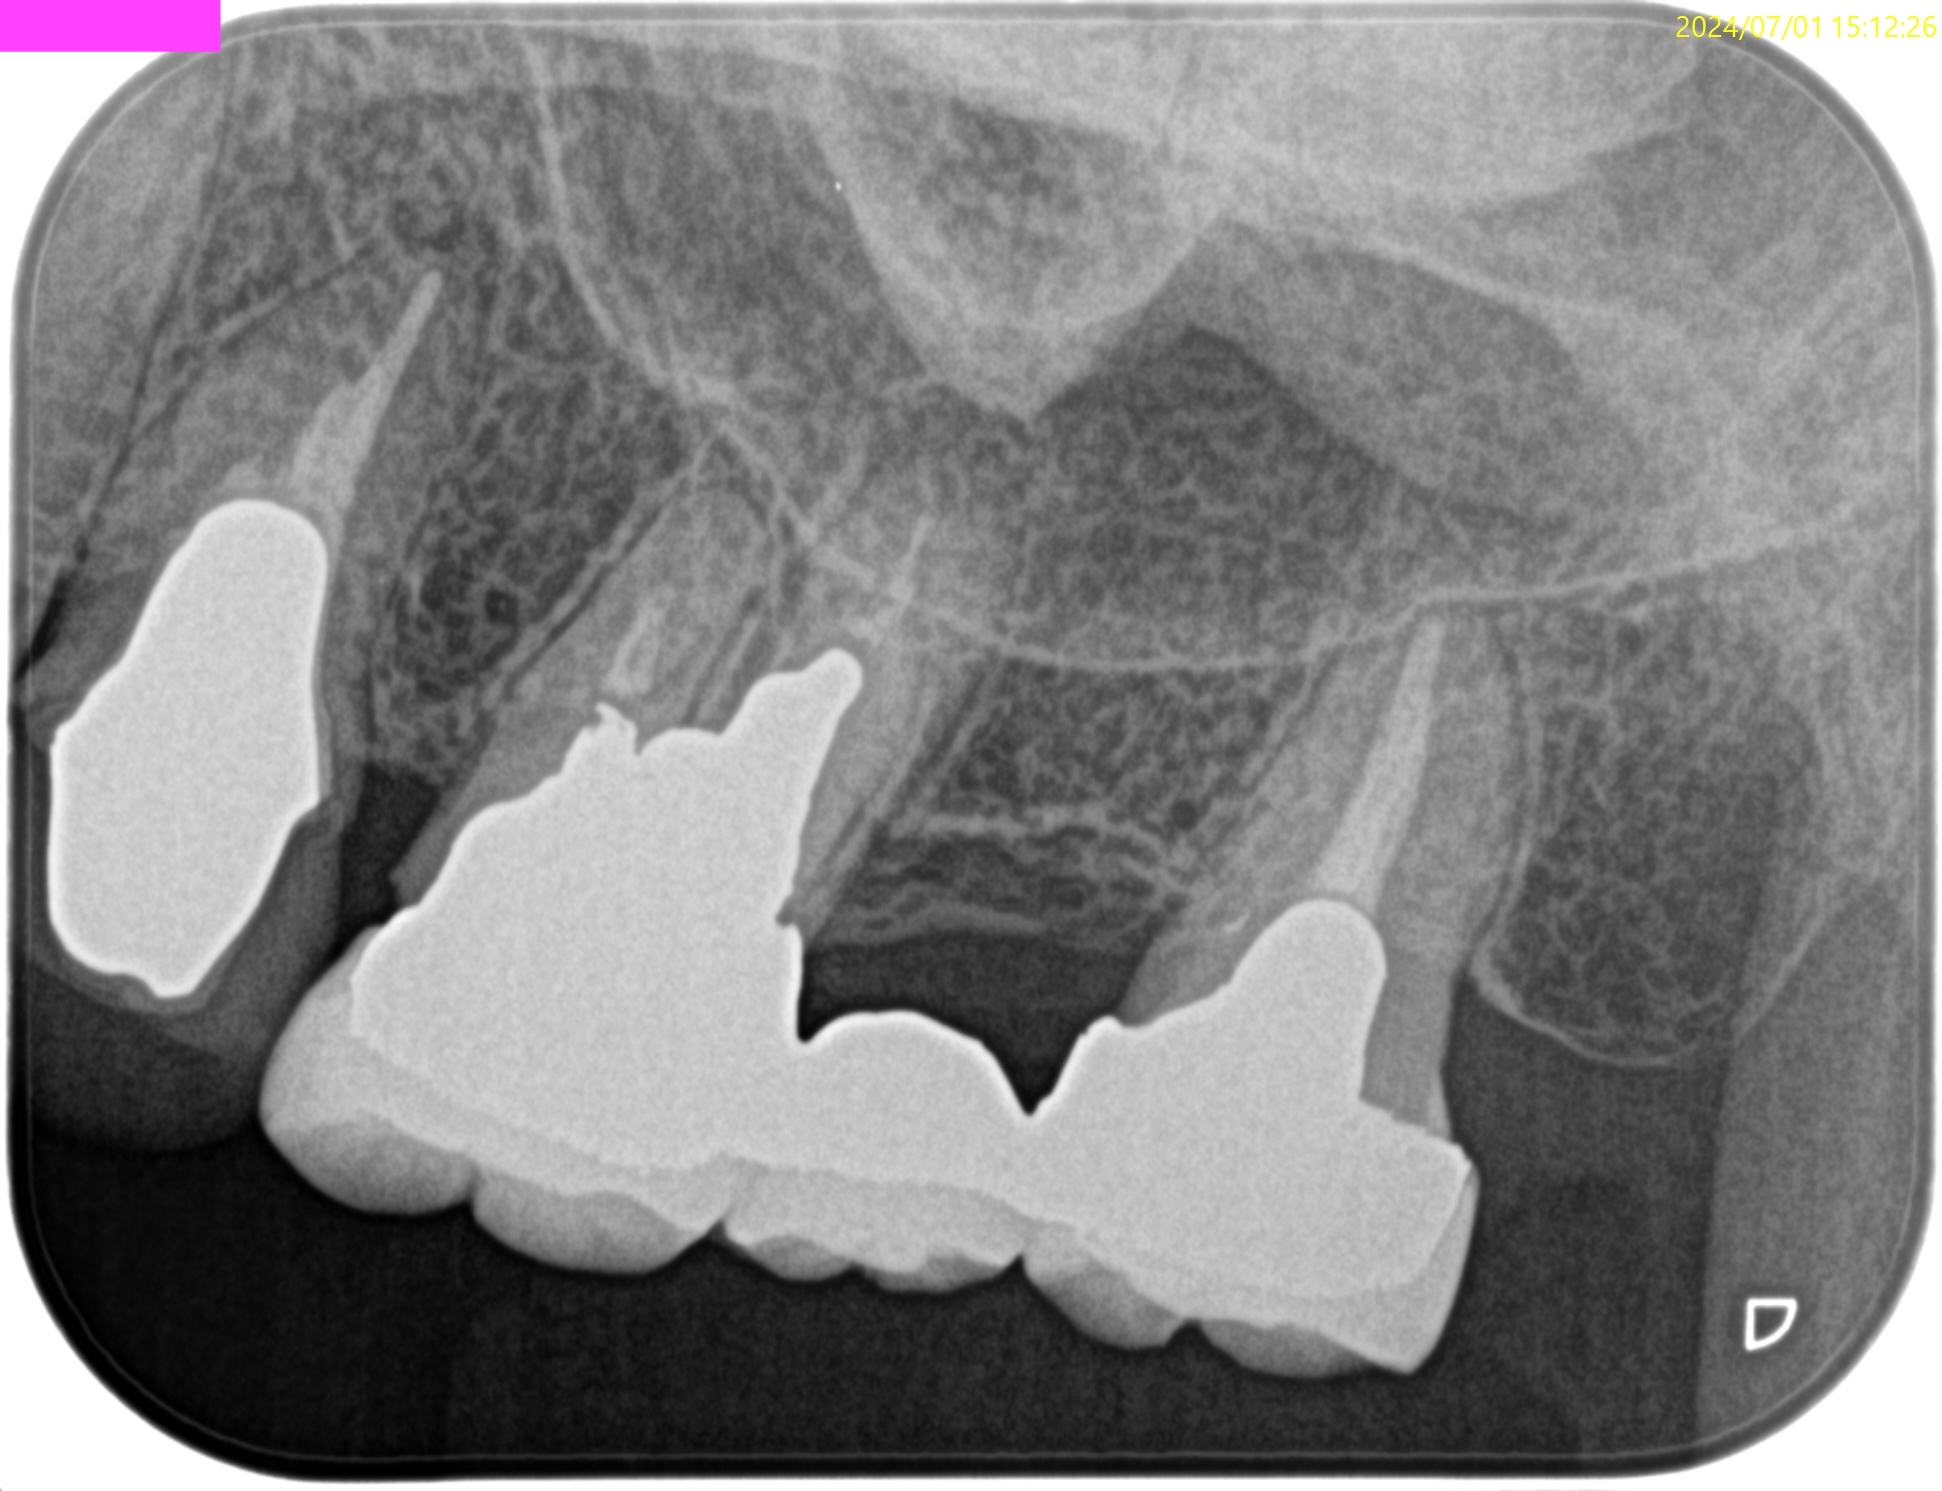

PA(2024.7.1)

CBCT(2024.7.1)

#3

MB

DB

P

MB,DB,Pと3根全てに病変がある。

しかも形成が不完全だ。

再根管治療が濃厚である。

#14

MB,DBには病変がないが、Pに存在する。

これは頭が痛い。

パラタルフラップも困難なケースだからだ。

#16

歯内療法学的診断(2024.7.1)

Pulp Dx: Previously treated

Periodical Dx: Symptomatic apical periodontitis

Recommended Tx: Re-RCT